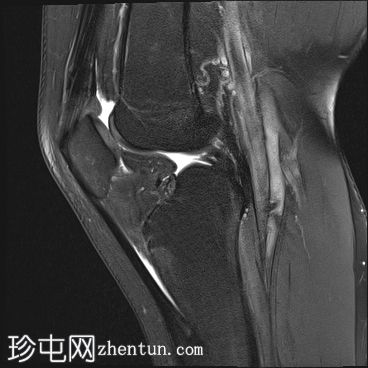

矢状面

T2

股骨内侧髁发育不全

胫骨髁间棘发育不全

腓骨头发育不全

前交叉韧带(ACL)和后交叉韧带(PCL)发育不全

髌腱延长,低位插入。

腘绳肌腱起源异常

外侧胫骨半月板韧带增厚;与外侧韧带(LCL)连接

术后可能出现股四头肌腱改变

本病例展示了腓骨半肢畸形(I型)的特征性表现。然而,腓骨半肢畸形可能伴有多种其他异常及异常组合,包括本例中的十字韧带发育不良。本文所述结果仅代表该疾病的一种可能变体。